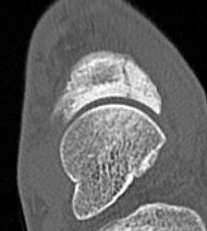

CT

Minimally displaced navicular stress fracture

Displaced navicular stress fracture